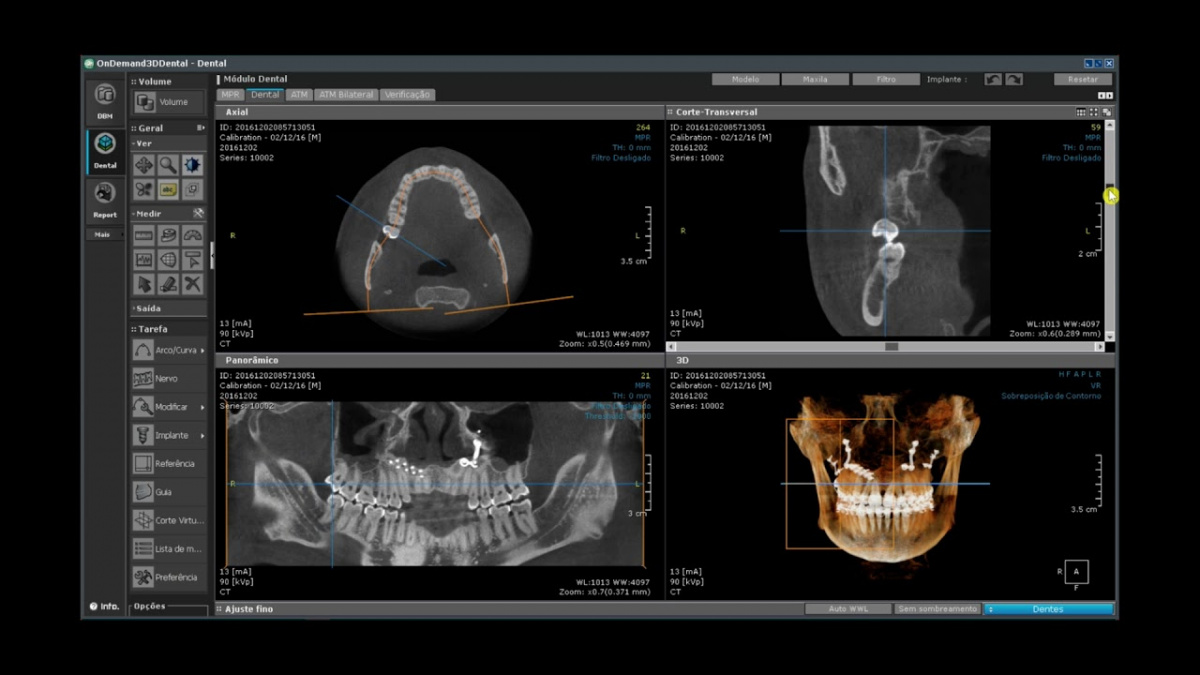

Немаловажным, а может главным вопросом, является универсальность программы-просмотровщика, в которой будут работать врачи-стоматологи. У Papaya 3D есть два варианта программ: Triana и OnDemand3D. Оба просмотровщика обладают схожим интерфейсом и имеют самые важные опции, а именно:

• режим MPR (многоплоскостная реконструкция). Именно здесь выстраивается интересующий участок челюсти или зуба для анализа.

• панорамный реформат. Возможность постройки классической и сегментарной панорамы позволяет продемонстрировать план лечения пациенту, а также оценить расположение анатомических структур на боковых кросс-секциях.

• модуль дентальной имплантации. Возможность виртуальной установки дентального имплантата с анализом окружающей костной ткани. В библиотеке представлен широкий спектр имплантологических систем с индивидуальной прорисовкой имплантата.

• выделение нижнечелюстного канала позволяет продемонстрировать расположение важного анатомического образования и определить зону безопасности при проведении лечения.

• функции плотности, линейных измерений и угла – необходимы для получения полноценной информации для последующего лечения.

• 3D режим – показывает трехмерную модель челюсти с целью определения аномалий, деформация, а также визуализации виртуальных имплантатов.

triana3.jpg triana4.jpg triana5.jpg

OnDemand3D (1).jpg OnDemand3D (2).jpg OnDemand3D 1.jpg

Таким образом обе программы являются простыми в пользовании, но обладающими обширным спектром возможностей для диагностики любыми специалистами-стоматологами. В данные программы происходит загрузка классических файлов DICOM 3.0, которые являются общепринятым форматом записи данных пациента. Это важный момент, так как позволяют врачу, имеющему полную версию программы загружать даже сторонние исследования и просматривать их в этих программах. Простота в освоении этих программ позволяет даже специалисту, не работающему раннее с этими программами, быстро адаптироваться и получить качественную информацию. Возможность выгрузки STL-файла дополнительно создает возможность интегрировать данные с цифровым ортопедическим протоколом.